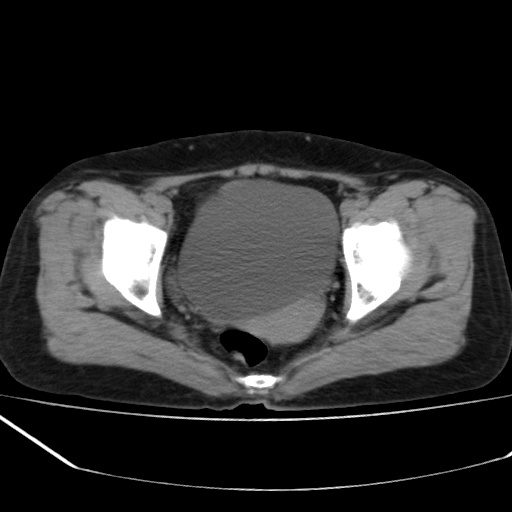

病人不肯增强,是不是膀胱右前方那一个

盆腔右前壁囊性占位,右耻骨轻微骨质吸收.性质选定,建议增扫或病理!!!!!

我只好报盆腔右前壁囊性占位,性质选定,建议增扫或病理.

膀胱右前方占位

病史?临床表现?膀胱右前方囊性占位,边缘光整,考虑良性,建议结合b超检查,既然要做手术,等手术结果吧,只是觉得手术仓促了些。

膀胱右前壁囊性占位,性质难定,要做手术,那就等手术结果吧.